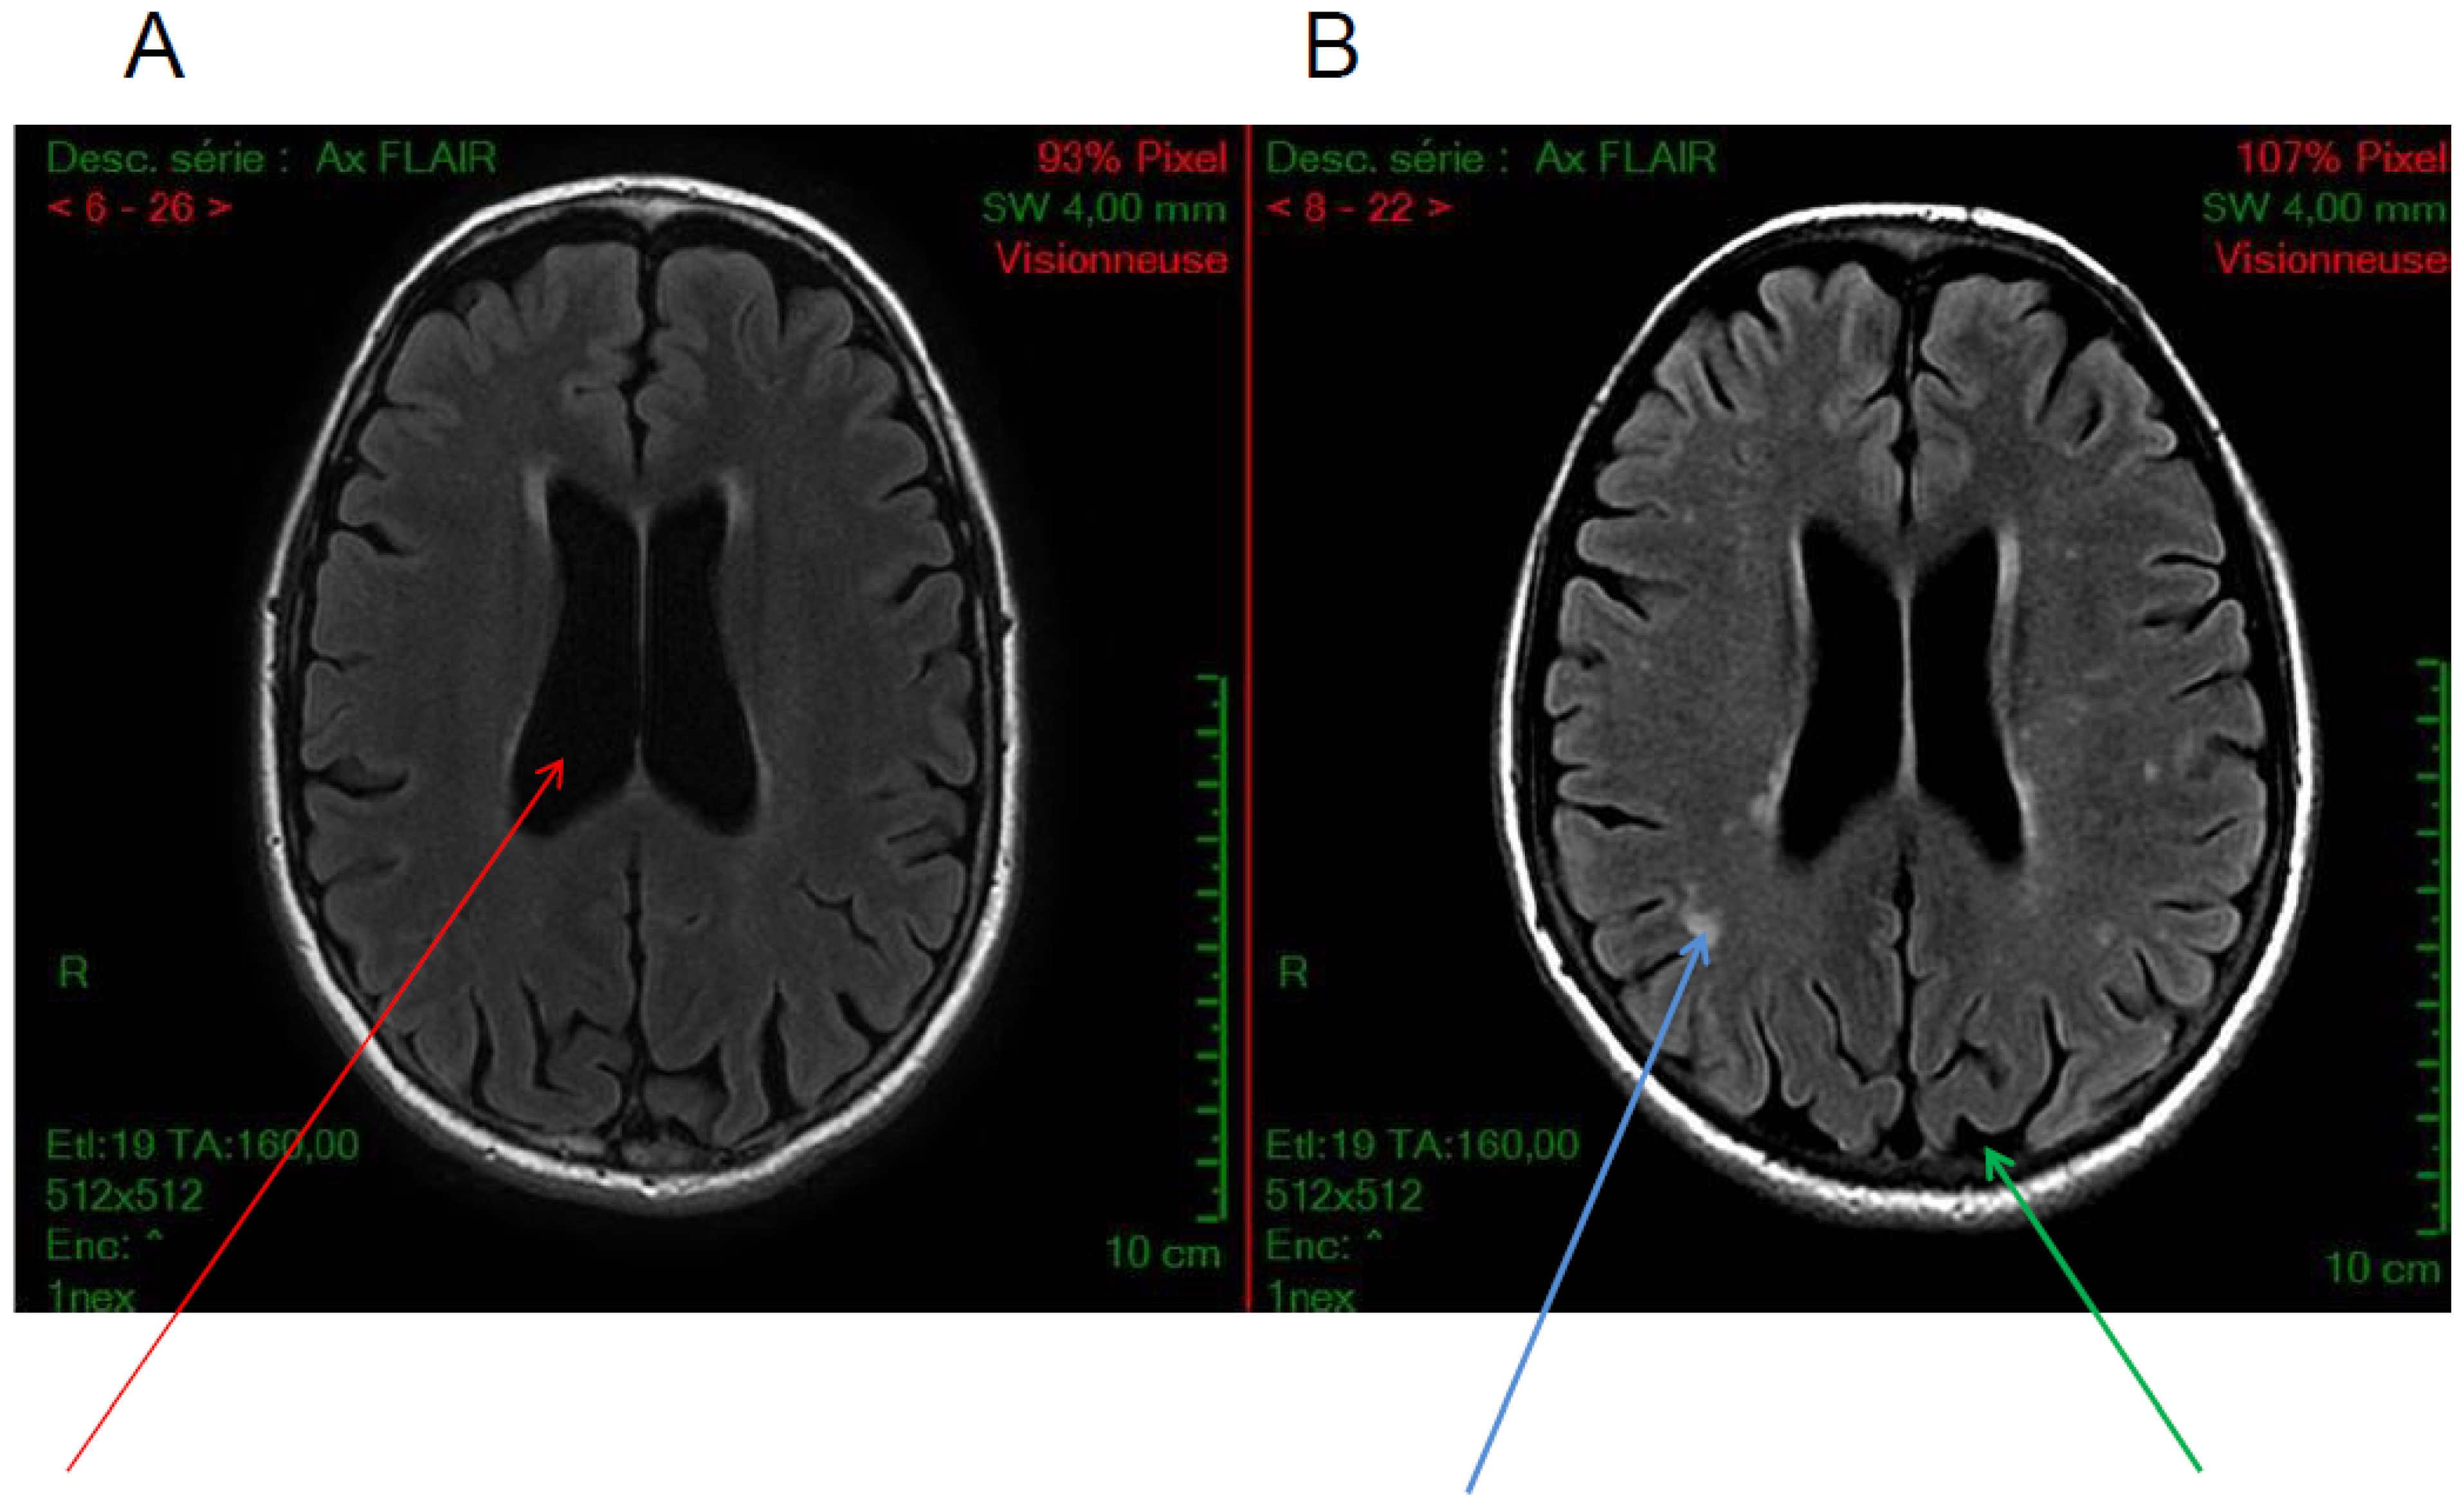

5.1. Calcifications

5.3. White Matter Hyperintensities

5.4. Others